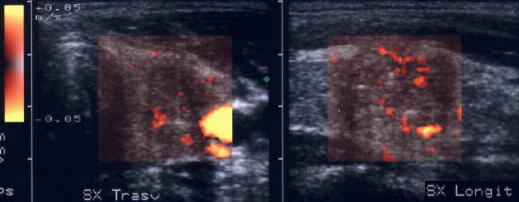

Lobul stang in proiectie longitudinala si trasversala.

Femeie de 39 ani. Tireotoxicoza in maladia lui Graves.

Cresterea in dimensiuni cu ecostrutura net hipoecogena prin edem inflamator, neomogena, cu striuri hiperecogene de fibroza.

Lobul stang proiectie longitudinala si longitudinala

Barbat de 52 ani. Tireotoxicoza in cadrul bolii Graves. Cresterea in volum a tiroidei, hipoecogena, difuz neomogena cu zone flocoase (alternanta neregulata de arii hipoecogene cu arii hiperecogene); la baza lobului drept este un mic nodul relativ hiperecogen.

Acelasi pacient. La doppler color, vascularizatie bogata, difuza in toata

glanda

Artera tiroidiana superioara stg.

Artera tiroidiana superioara dreapta.

Acelasi

pacient. La doppler color, vascularizatie bogata, difuza in toata glanda

Examen doppler cu calcul al al velocitatii instantanee a arterelor tiroidiene

superioare.

De notat cresterea velocitatii (0,60 m/s).